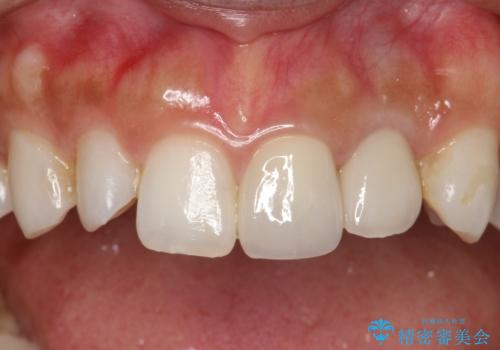

- 左上の前歯が外れそうとのことで来院されました。

レントゲンを撮影すると、不適合のかぶせ物が装着されており、根管治療も不十分でした。

左上の1番目、2番目の歯を根管治療からの再治療を行う計画としました。